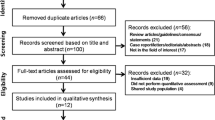

The differentiation between acute benign osteoporotic and malignant vertebral fractures is sometimes challenging, since they both occur without adequate trauma and are common in the elderly population. Conventional X-ray is the first imaging method to depict vertebral fractures, however it lacks specificity. CT allows better delineation of osseous destruction in neoplastic fractures, however it is not always possible to define the exact cause of the fracture. MRI is more specific as well as more sensitive in detecting especially discrete osteoporotic fractures. In most cases the combination of morphological signs in CT and MRI allows the determination of a benign or malignant cause of the vertebral fracture. However, there remain uncertain cases with contradictory imaging features. In the following chapter, we discuss the morphological signs which help in the differentiation between acute benign and neoplastic vertebral fractures. We describe the latest techniques such as diffusion-weighted, chemical-shift, and perfusion MRI as well as nuclear-medical techniques.